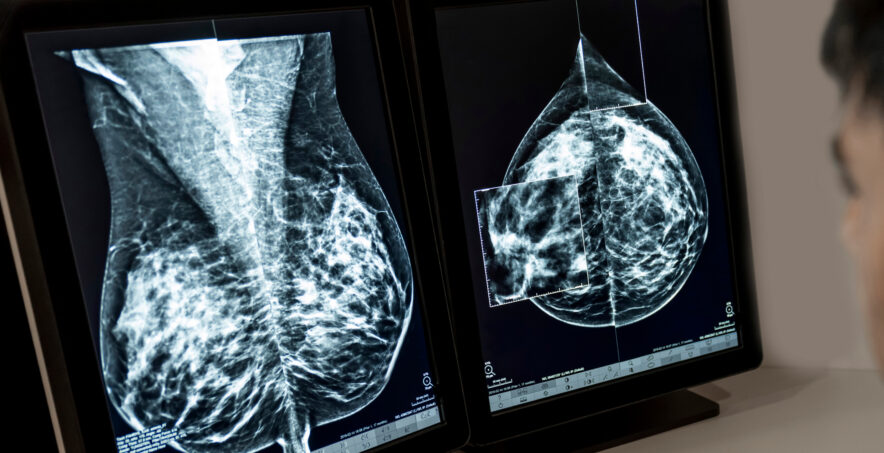

This month has transformed the landscape for breast screening, with the official guideline from the National Comprehensive Cancer Network (NCCN) recommending advanced follow-up with MRI for women with high risk (greater than or equal to 1.67 percent in 5 years) based on AI assessments of mammograms. Across two million mammograms in countries with highly diverse populations, the Mirai algorithm, developed by Jameel Clinic research affiliate Adam Yala (then a graduate student at MIT) and Jameel Clinic AI faculty lead Regina Barzilay, is the core technology that brought about this change.

Mirai cuts through the Gordian knots of debate and resource allocation to identify which women are at high risk and require monitoring, and which women can be reassured that they have lower risk. Family history only accounts for 15 percent of breast cancers and breast cancer is affecting younger women at higher rates. In the U.S., this is a huge step towards women getting this information without exorbitant private expenses for MRIs. In more resource-constrained countries, this can be used to triage access to limited resources such as 3D mammography and more frequent screenings.